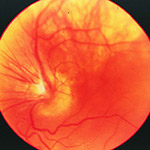

Neovascularization of the Optic Nerve Head

New blood vessel growth on the optic nerve head.